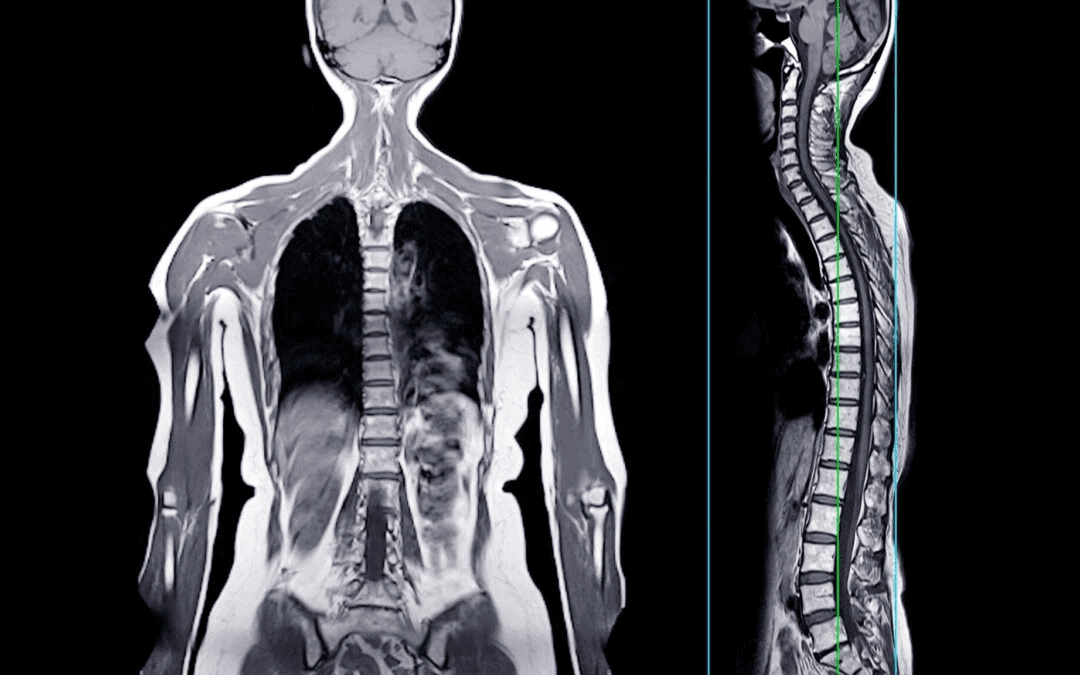

A Full Body MRI is a comprehensive, non invasive scan that visualizes major organs, soft tissues, blood vessels, and structural systems in a single session. It is designed to detect hidden abnormalities before symptoms appear.

The scan examines the brain, spine, liver, kidneys, pancreas, heart structures, pelvic organs, and musculoskeletal regions. It identifies tumors, cysts, inflammation, degenerative changes, vascular irregularities, and silent disease markers.

Entire spine